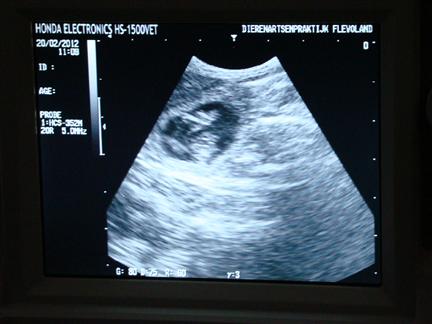

| hier een ander pupje |

| Je kon het hartje ook al fanatiek zien kloppen |

op basis van de ontwikkeling van het hartje is de uitgerekende datum op 22 maart 2012 vastgesteld |